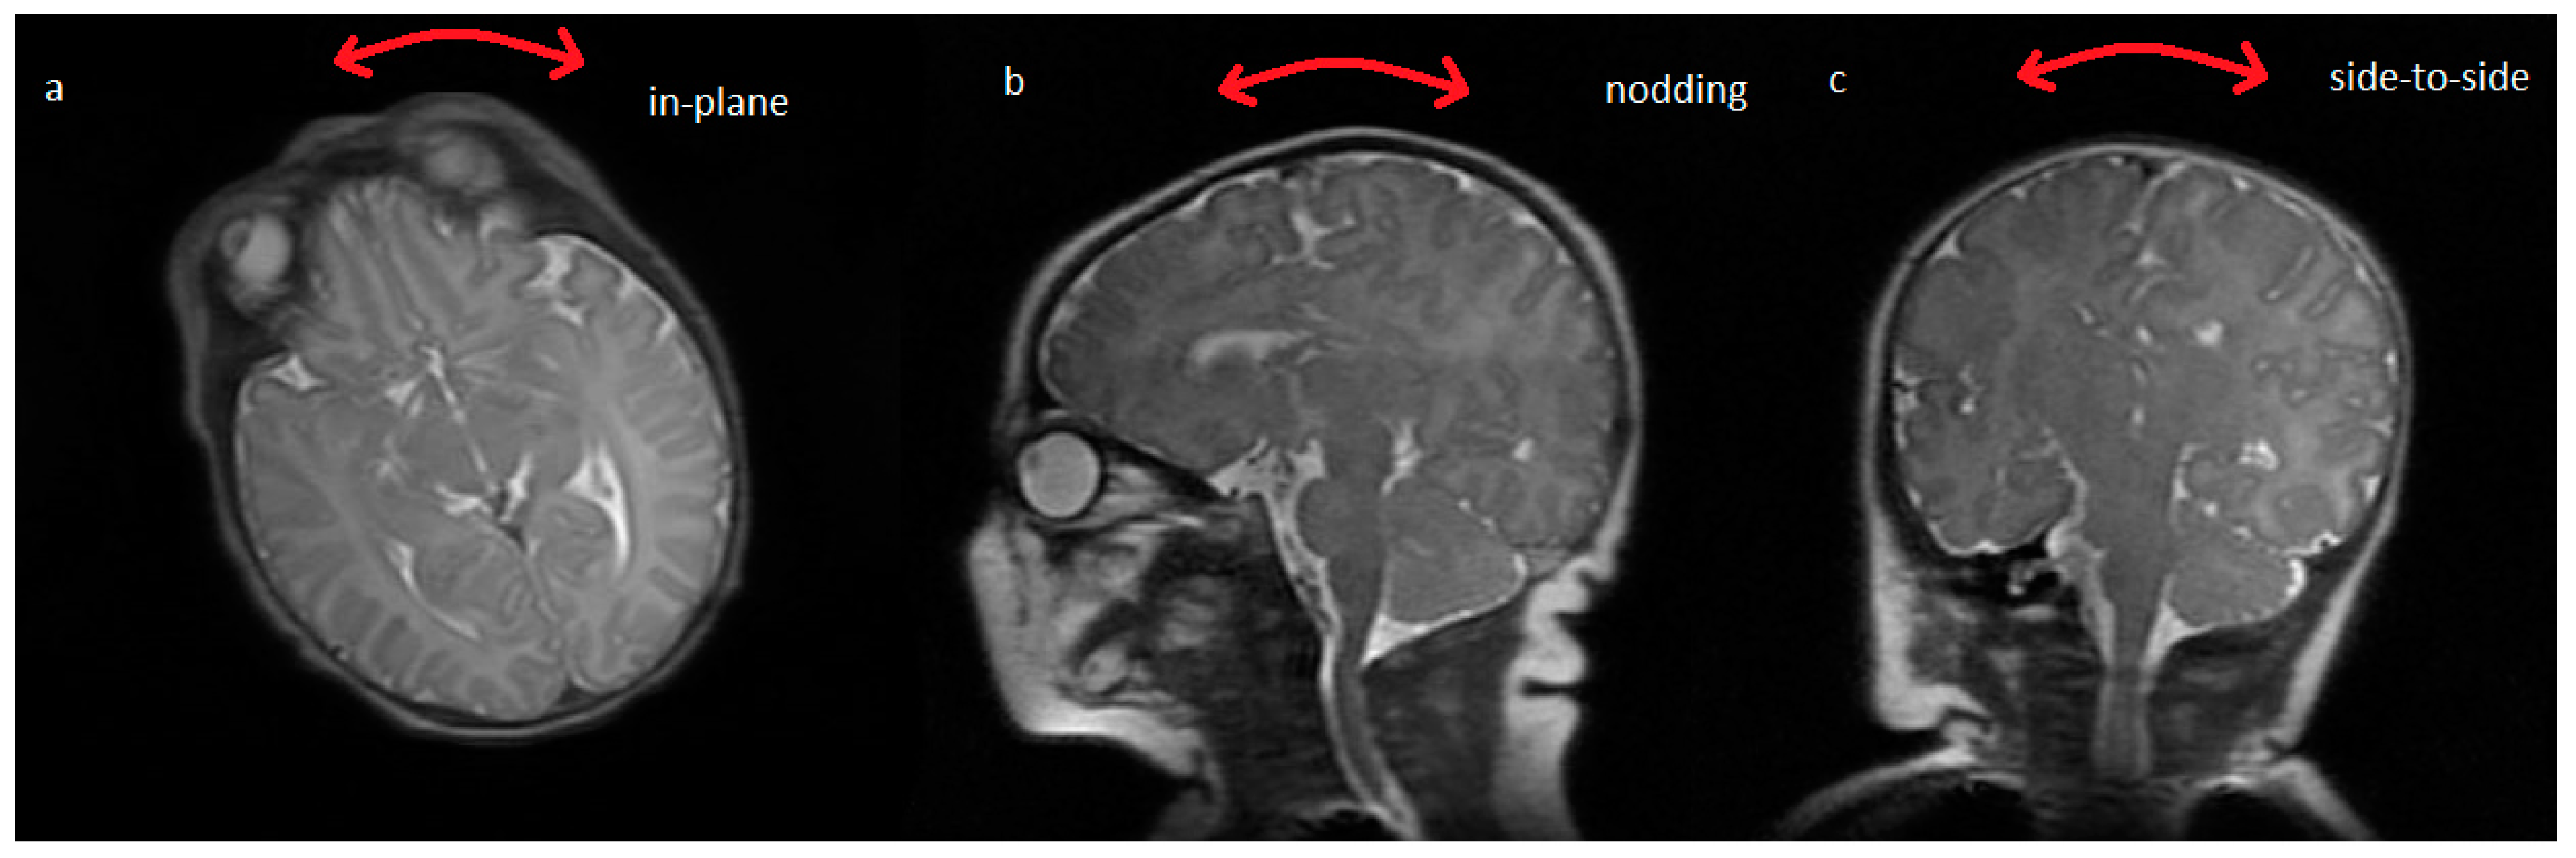

Typical artifacts obtained during neonatal in-plane head rotation, as observed visually during scanning, are shown in Figure 3 [11].

Figure 3. The image on the left is a Fast Spin Echo (FSE) image acquired over two minutes showing no motion artefact, the image in the middle is the same sequence showing artifact due to neonatal in-plane rotational head movement, as noted visually, which is commonly seen when imaging neonates [11]. The image on the right is a single shot fast spin echo showing no motion artefact but with inferior signal to noise ratio and resolution.